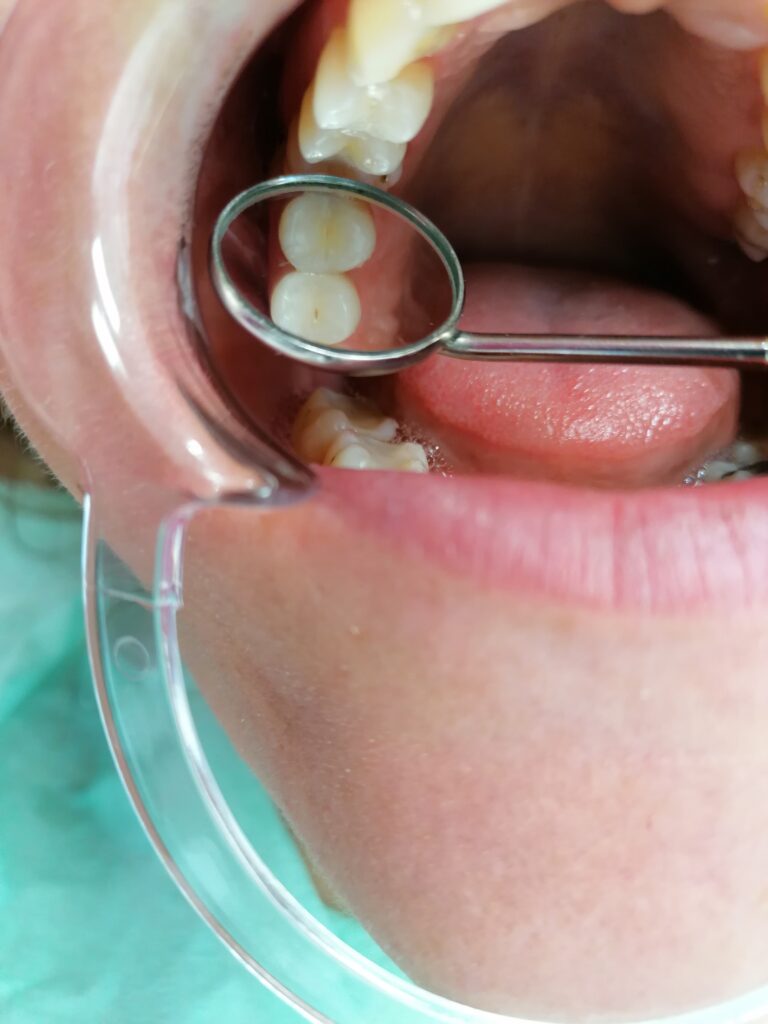

- Kompozitne(bele) plombe

- Lečenje kanala korena zuba(endodoncija)

Konzervativna stomatologija je grana stomatologije koja obuhvata bolesti zuba i endodonciju. Najčešći uzrok nastanka oboljenja zuba je zubni karijes. U zavisnosti od stepena rasprostranjenosti karijesa u zubnim tkivima, zavisiće i sam tok terapije. Ukoliko karijes nije zahvatio „zubni živac“ ili pulpu zuba, plan je preparisati kavitet i postaviti ispun koji se još u narodu zove plomba. Ukoliko karijes jeste zahvatio pulpu zuba, plan je ekstirpirati(izvaditi) „živac zuba“, adekvatno obraditi kanale i nakon toga napuniti ih gutaperkom i silerom.